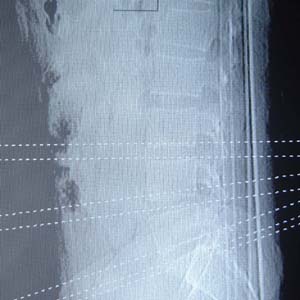

本人的片子,腰腿痛多年,时轻时重。请各位老师发表高见!

1.l4~5间盘膨出伴突出(中央型)

2.l5-s1后纵韧带钙化.